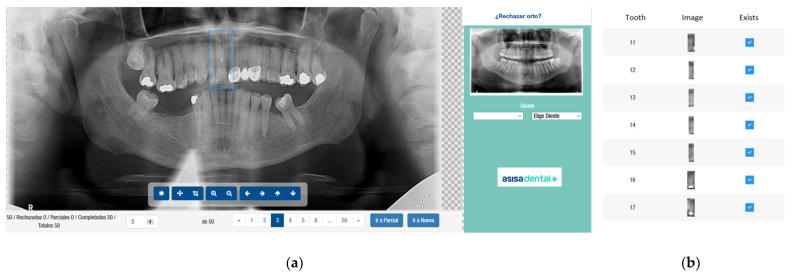

一种采用卷积神经网络对牙齿有无进行影像学检测的验证方法。

A Validation Employing Convolutional Neural Network for the Radiographic Detection of Absence or Presence of Teeth.

Dental radiography plays an important role in clinical diagnosis, treatment and making decisions. In recent years, efforts have been made on developing techniques to detect objects in images. The aim of this study was to detect the absence or presence of teeth using an effective convolutional neural network, which reduces calculation times and has success rates greater than 95%. A total of 8000 dental panoramic images were collected. Each image and each tooth was categorized, independently and manually, by two experts with more than three years of experience in general dentistry. The neural network used consists of two main layers: object detection and classification, which is the support of the previous one. A Matterport Mask RCNN was employed in the object detection. A ResNet (Atrous Convolution) was employed in the classification layer. The neural model achieved a total loss of 0.76% (accuracy of 99.24%). The architecture used in the present study returned an almost perfect accuracy in detecting teeth on images from different devices and different pathologies and ages.

摘要

口腔放射成像在临床诊断、治疗及决策过程中发挥着重要作用。近年来,人们致力于开发图像中物体检测技术。本研究的目的是使用一种有效的卷积神经网络来检测牙齿的有无,该网络可减少计算时间且成功率大于95%。共收集了8000张口腔全景图像。由两位具有三年以上普通牙科经验的专家对每张图像及每颗牙齿进行独立且手动的分类。所使用的神经网络由两个主要层组成:目标检测层和分类层,分类层以前者为支撑。目标检测采用了Matterport Mask RCNN。分类层采用了ResNet(空洞卷积)。该神经模型的总损失率为0.76%(准确率为99.24%)。本研究中使用的架构在检测来自不同设备、不同病理情况及不同年龄的图像中的牙齿时,返回了几乎完美的准确率。